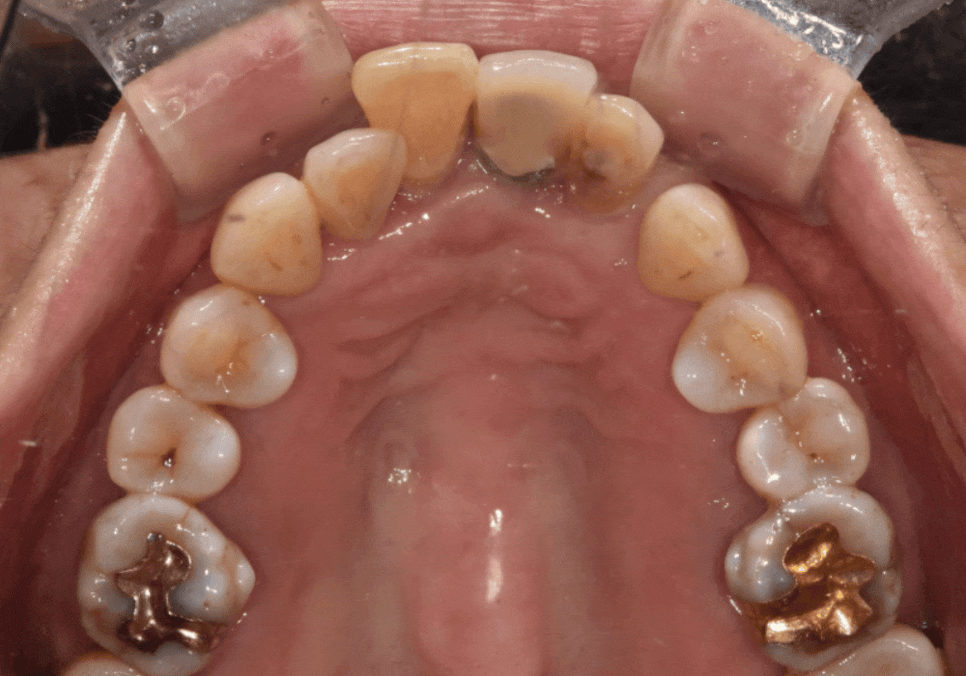

이 환자분은 “앞니가 흔들린다"는

불편감으로 오셨습니다.

확인해 보니 왼쪽 앞니는

오래전에 이미 임플란트를 해두신 상태였고,

230826

임플란트 양옆의 치아가

흔들리는 상황이었습니다.

문제는 기존 임플란트 보철이

예전 치아 배열 기준으로

제작돼 있었다는 점이었는데요,

그 보철을 기준으로 새 보철을 맞추면

최종 결과가 다시

앞니가 튀어나와 보이는 형태로

갈 가능성이 있었습니다.